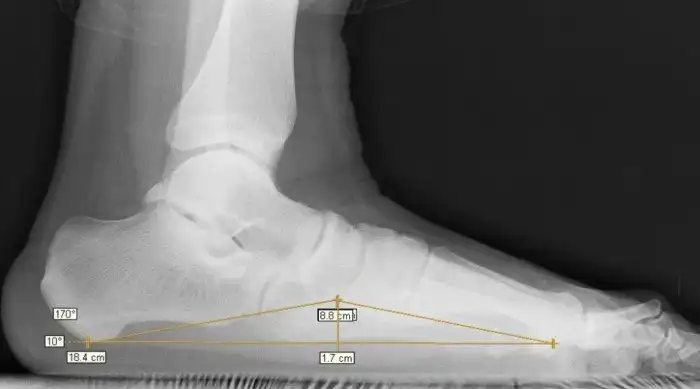

В здоровой стопе природное соединение подвижных костей составляет два свода. Они выполняют амортизирующую функцию. Врожденные пороки или внешние факторы могут привести к тому, что стопа становится плоской и соприкасается с поверхностью — соотвественно, амортизационная функция перекладывается на другие части тела, которые не предназначены для таких нагрузок. С этого и начинаются настоящие проблемы для всего организма.

Телу приходится искать какую-то амортизацию при ходьбе. Довольно быстро развивается искривление позвоночника, лордоз, кифоз и сколиоз.